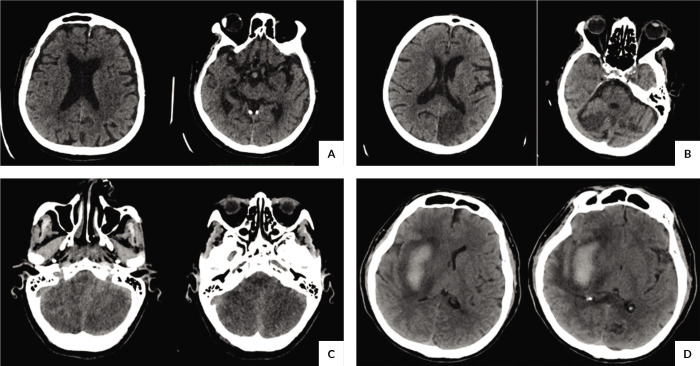

Methods: We conducted a cross-sectional study analyzing CT images of COVID-19 patients with neurological symptoms. Among 51 included patients, plain CT scans were predominantly used, revealing no acute infarcts or hemorrhages in the majority, while frontal lobe involvement was notable in cases with pathology. Chronic infarcts or ischemic changes were observed in over half of the cases, primarily affecting the anterior circulation. Only one case of meningitis was documented.

Results: In the final analysis, 51 patients met the inclusion criteria out of the initial 64 enrolled. The study population, predominantly male with a mean age of 58.02 ± 20.87 years, mainly comprised patients solely diagnosed with COVID-19. Plain CT scans were favored over contrast-enhanced scans (76.50%, n = 39). While most patients had no acute infarcts or hemorrhages, the frontal lobe was commonly affected among stroke patients (9.8%, n = 5). Additionally, a significant portion of patients without acute stroke findings exhibited chronic infarcts or ischemic changes (57.69%, n = 15).

Conclusions: This study sheds light on the radiological patterns of CNS involvement in COVID-19 patients, highlighting frequent frontal lobe involvement possibly attributed to hypercoagulability and endotheliitis. Further research with larger sample sizes and MRI utilization is recommended to enhance our understanding of CNS manifestations in COVID-19. This study contributes to understanding COVID-19 neurological sequelae, particularly in terms of radiological patterns, among patients presenting with neurological symptoms. The findings highlight the need for comprehensive evaluation and management of neurological complications in COVID-19 patients.